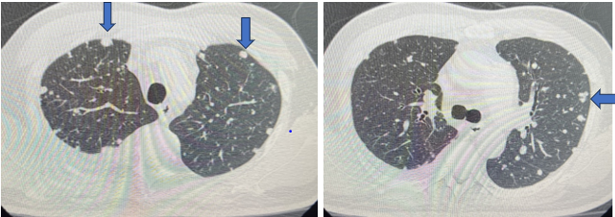

• Hình ảnh Cắt lớp vi tính lồng ngực:

Hình 2: Nốt mờ rải rác hai bên phổi, kích thước từ 0,5 x 1 cm (mũi tên xanh), Tràn dịch màng phổi phải